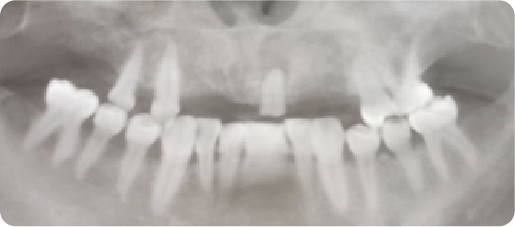

Multi-unit Dental Implant Case

BEFORE

VS

AFTER

Name:MS DengAge:31

Evaluation: Long-term use of a removable denture has led to compromised mastication and severe alveolar bone resorption.

Treatment Plan:The solution involves three dental implants that anchor a five-tooth bridge.Two artificial teeth are suspended between the implant-supported crowns, restoring all five missing teeth.

Patient Feedback:Tought&Feel like natural teeth.Unlike removable dentures, implant-supported teeth are designed for lasting comfort, security, and a natural appearance—without slipping or the need to grind down adjacent teeth.